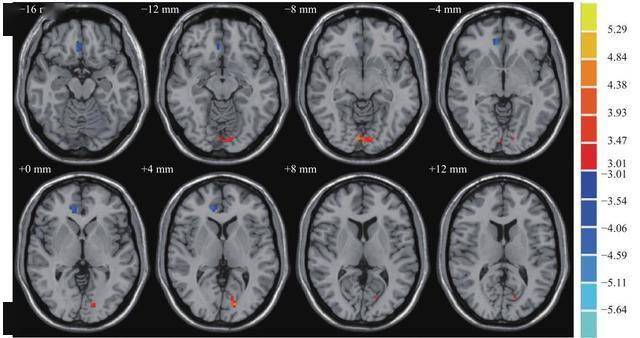

二头颅MRI检查 头颅MRI即头部核磁共振检查,能够提供更为详细和精确的脑部图像与CT相比,MRI在显示脑部软组织结构神经和血管等方面更为优越,对于诊断脑肿瘤脑梗塞神经病变等疾病具有重要价值三脑电图检查 脑电图检查主要用于评估脑部电活动通过记录大脑神经细胞的电活动,有助于诊断癫痫。

MRI检查的主要部位包括脑部脊柱关节软组织以及内脏器官脑部MRI可以清晰地显示脑部的结构,包括脑组织的细节,对于诊断脑部疾病如脑卒中脑肿瘤等具有很高的准确性和敏感性脊柱MRI常被用来检查脊柱疾病,如椎间盘突出脊柱裂等,还可以评估脊柱狭窄的程度和位置关节MRI能够清晰地显示关节;价格范围单纯的头颅MRI检查费用通常在400元左右,这个价格是大致的范围,可能会因地区和医院级别的不同而有所差异医保政策该检查费用在医保范围内,可以报销,这有助于减轻患者的经济负担检查目的脑部全面检查的核磁共振主要用于诊断脑部疾病,如脑肿瘤脑血管疾病脑外伤等,其诊断性能很高注。

磁共振正常不能排除脑部所有疾病以下是对这一结论的详细解释能排除部分器质性疾病磁共振成像是一种先进的医学影像技术,能够清晰地显示脑部的结构细节通过MRI检查,医生可以观察到脑部是否存在占位性病变,如肿瘤脑出血脑梗塞等器质性疾病如果MRI结果显示正常,通常可以排除这些明显的器质性;早期发现脑部功能性变化脑功能MRI检查是一种无创的功能性检查,能够早期发现脑部的功能性异常,如血流代谢或神经活动的改变,有助于医生在疾病早期阶段进行诊断辅助早诊断早治疗通过脑功能MRI检查,医生可以更早地识别出脑部病变,从而为患者提供及时的治疗,有助于提高治疗效果和预后提供多种。